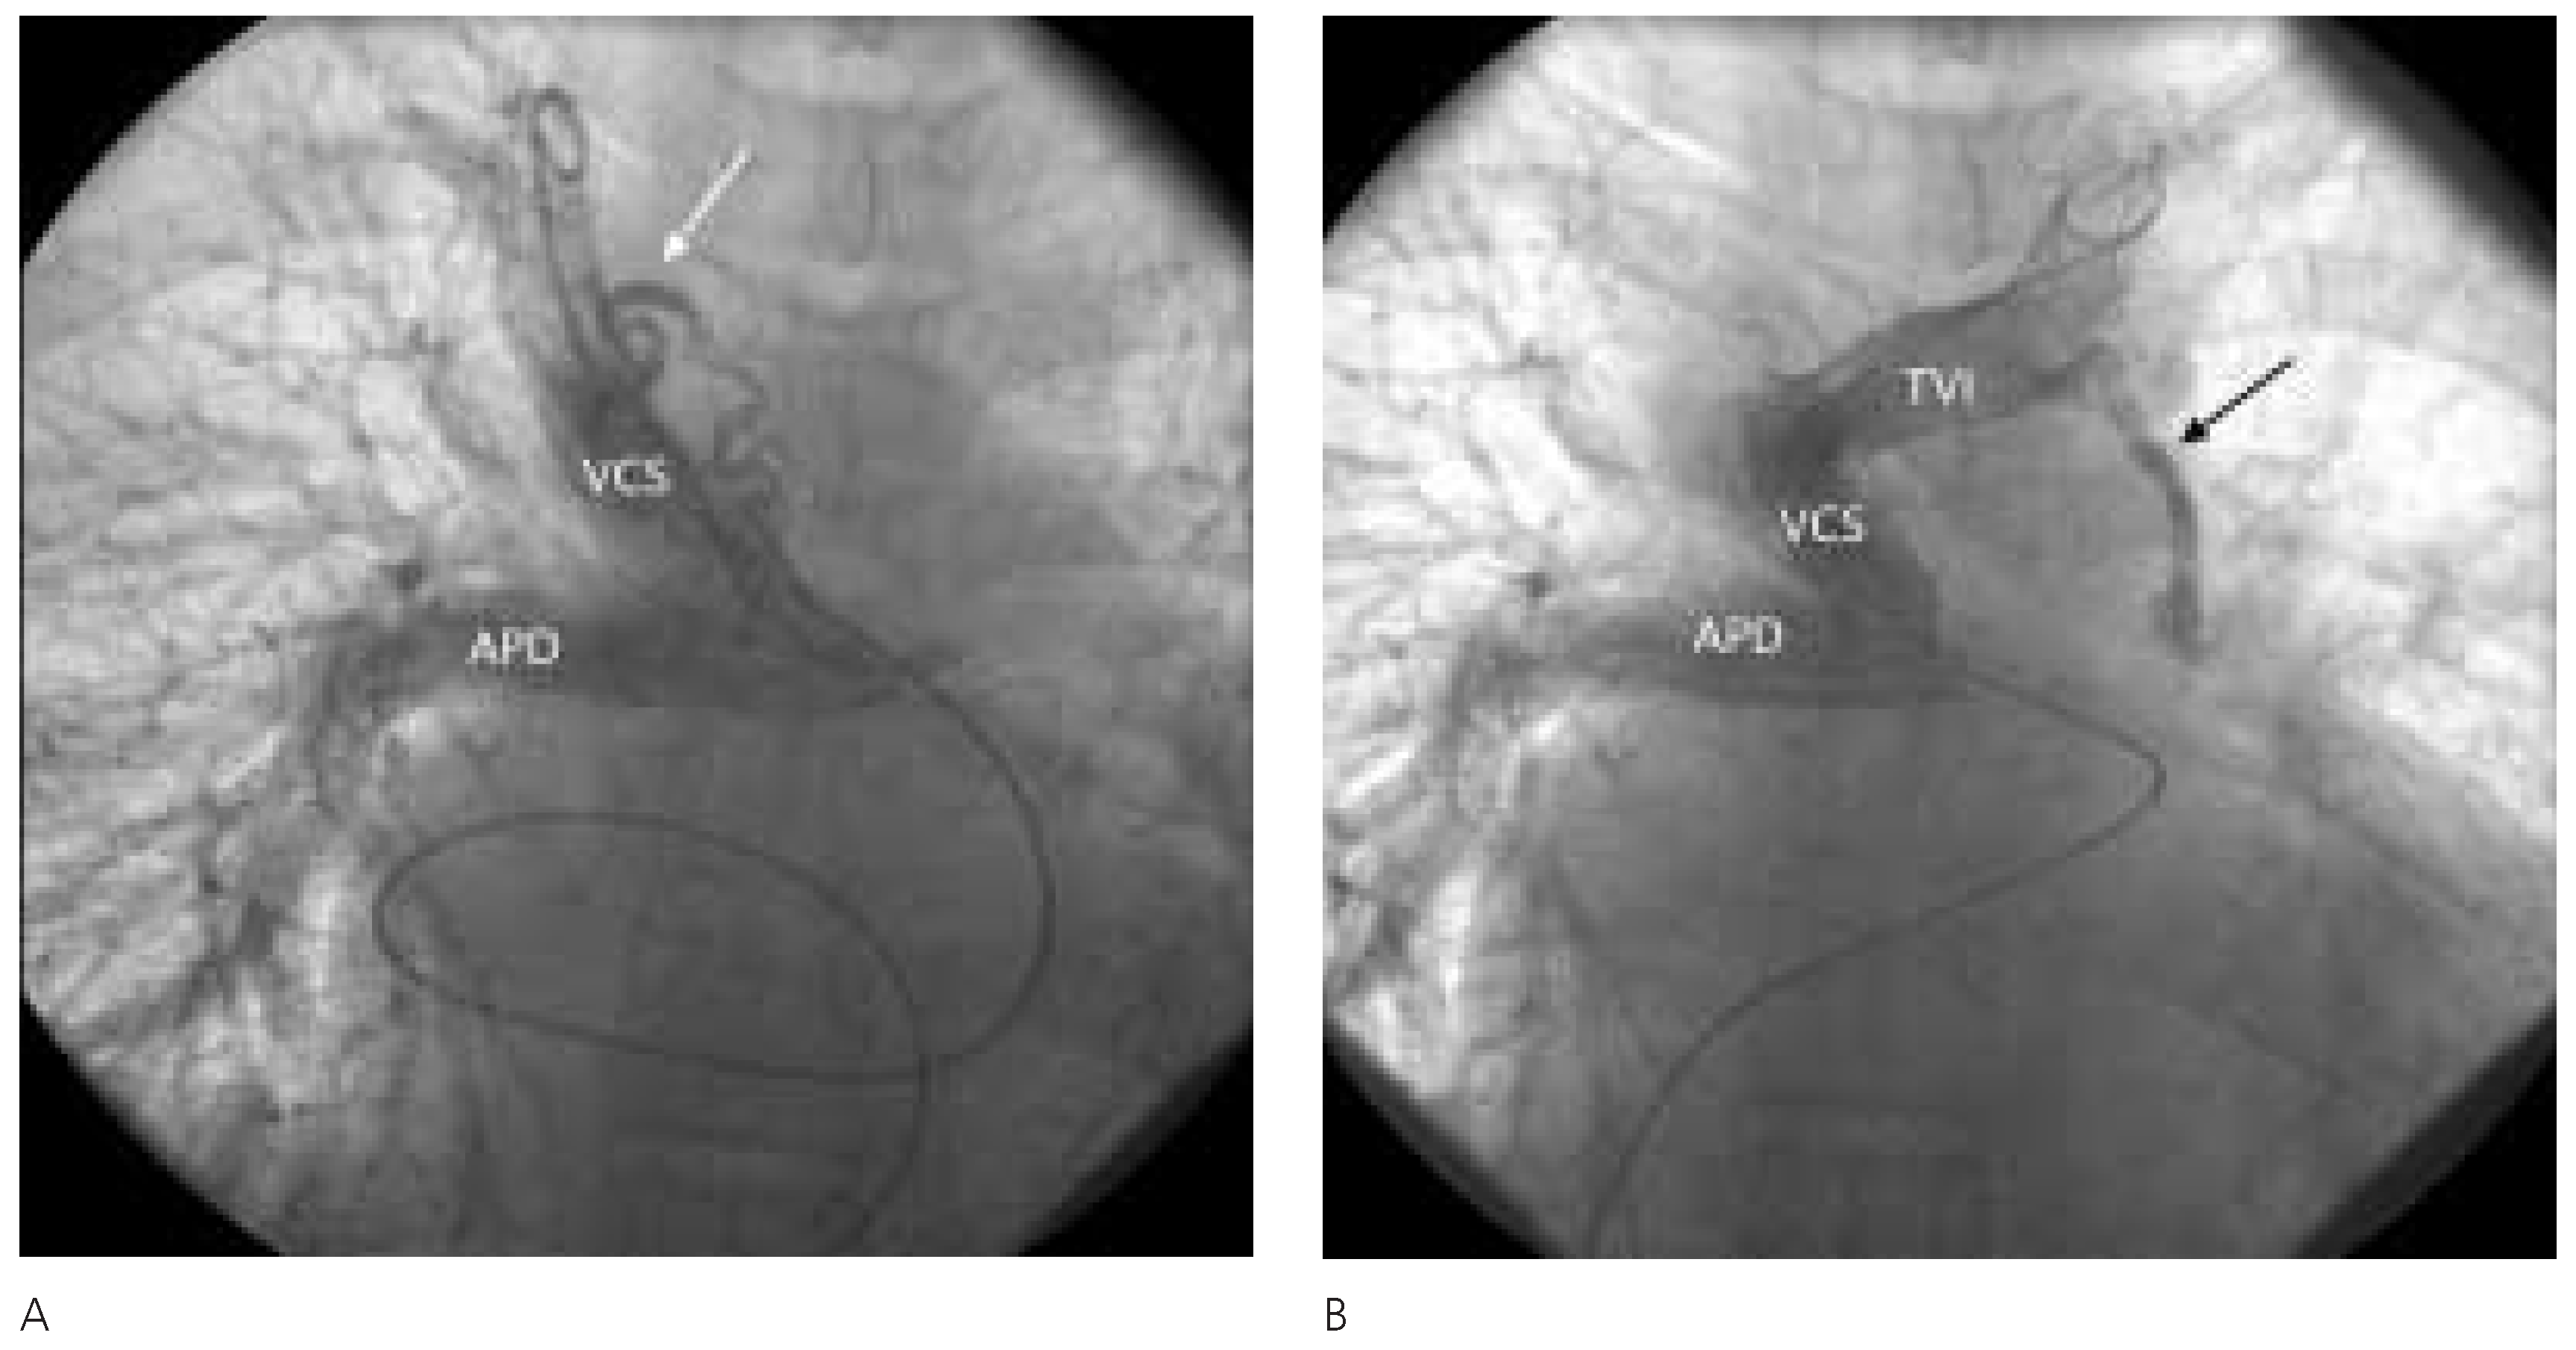

Description du cas